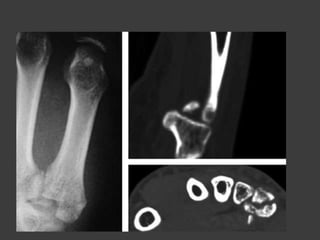

Fx diafisarias de los

metacarpianos

Transversales

Oblicuas

conminuta

Metodos de reducción

Transversales

Oblicua

Conminuta